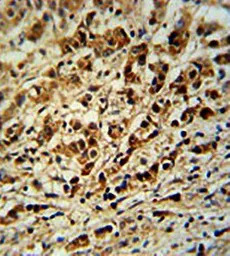

IHC-P analysis of human breast carcinoma tissue using GTX16209 AVL9 antibody.